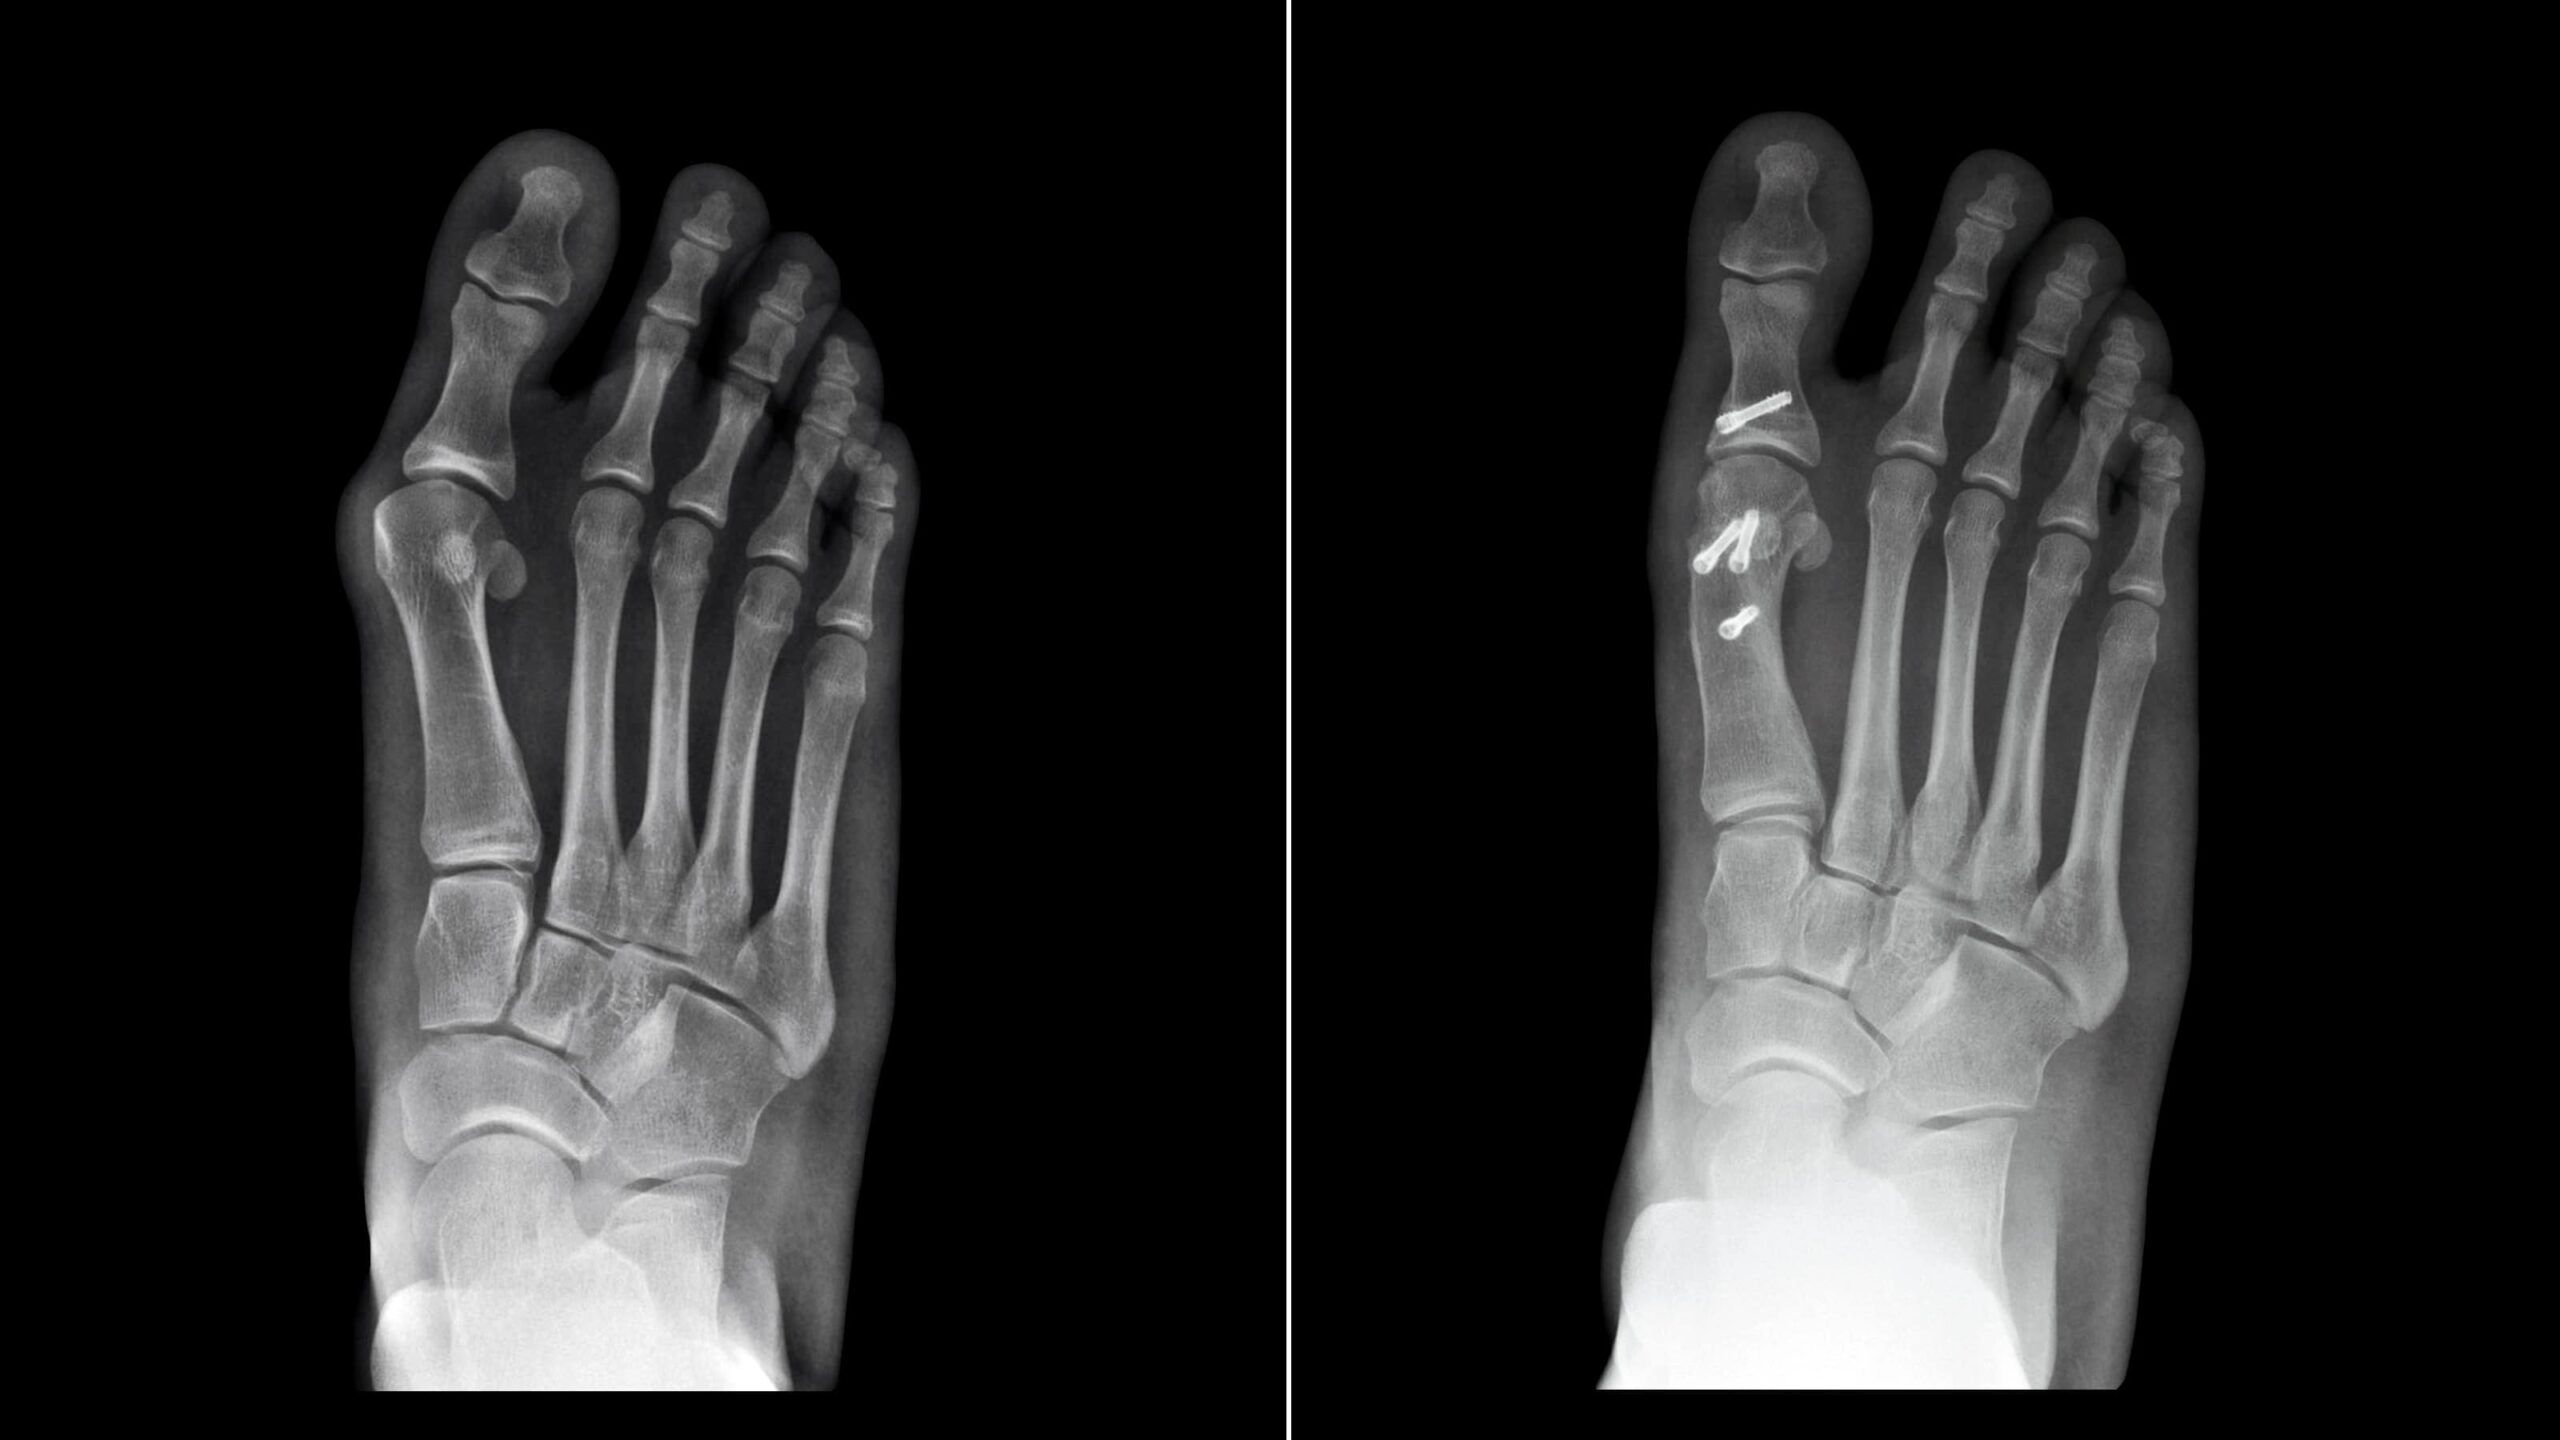

- Foot and Ankle Osteotomy:

- Corrects deformities like bunions, flat feet, or clubfoot.

Procedure Overview

- Preoperative Evaluation:

- X-rays, CT scans, or MRIs are used to assess the deformity.

- Surgical Steps:

- Under anesthesia, the surgeon makes an incision at the affected area.

- The bone is cut and repositioned using metal plates, screws, or rods for stabilization.